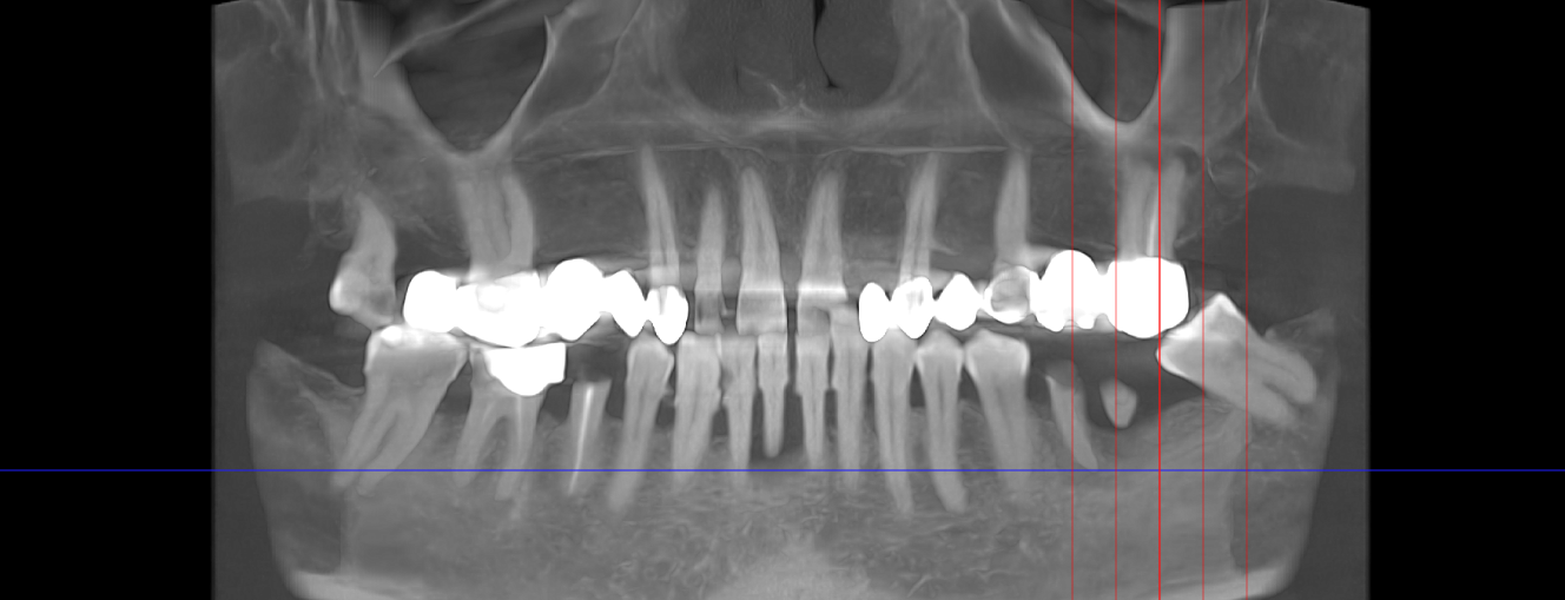

- Consultație, radiografie și plan de tratament personalizat

- Șlefuirea dinților de susținere sau inserarea implanturilor

- Ai unul sau mai mulți dinți lipsă într-o zonă în care dinții vecini sunt sănătoși și stabili